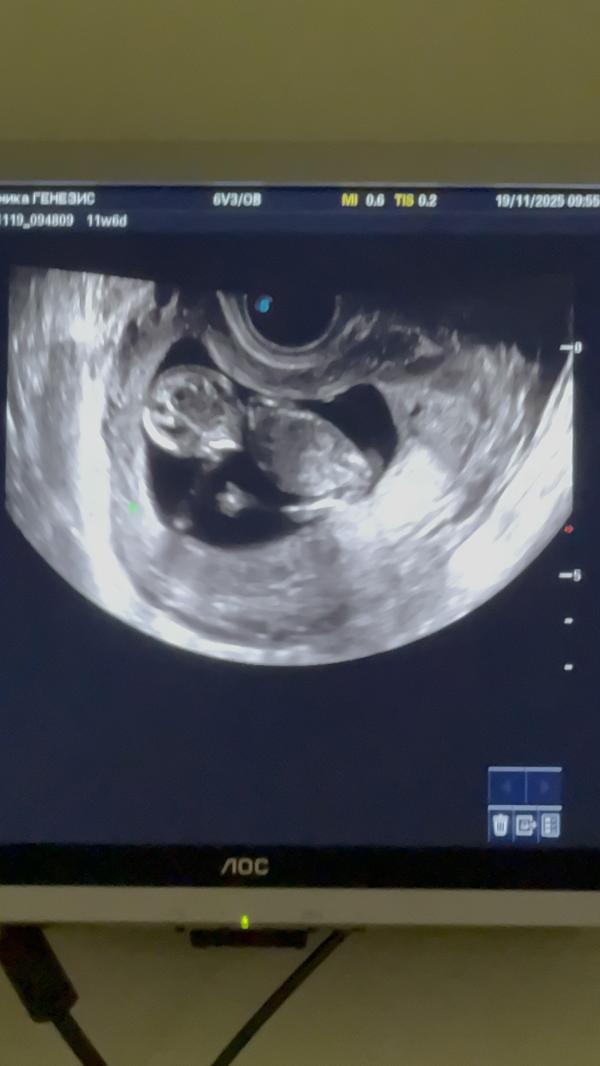

Малявочка говорит что у нее все супер 🥹😸показала 👍🏼